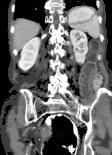

Plain X ray of a cecal volvulus

CT scan of a cecal volvulus